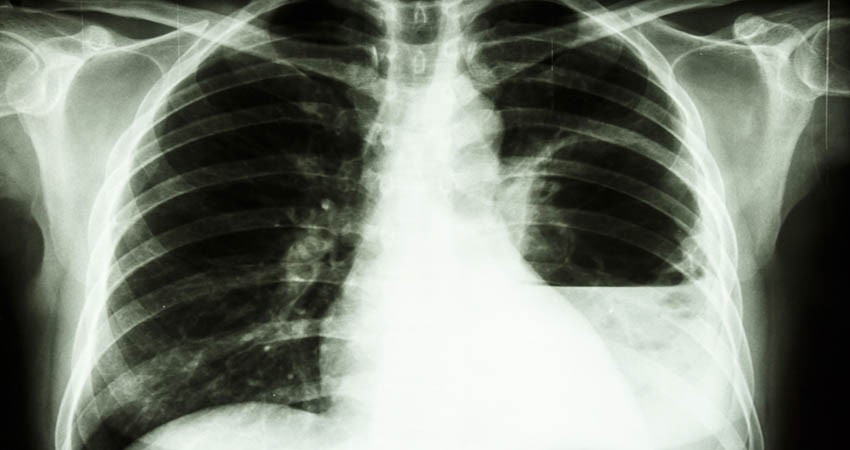

En este sentido dijo que las personas que presenten fiebre súbita, lesiones en tejidos blandos sin respuesta, complicaciones respiratorias de evolución rápida deben acudir a consulta para una valoración profesional, al puntualizar que entre las medidas preventivas resalta evitar el contacto con suelo, agua contaminada y/o estancada, especialmente después de lluvias; usar botas impermeables durante y después de inundaciones o tormentas para prevenir la infección. Usar calzado y guantes protectores al realizar trabajos en el jardín o agricultura. Proteger heridas abiertas, cortes o quemaduras. Lavar a fondo cualquier herida abierta, corte o quemadura que entre en contacto con el suelo, así como evitar beber agua no tratada y comer alimentos crudos o mal cocidos.

Luego de presidir la sesión del Comité Estatal de Epidemiología (CEVE), en la que se emitió este aviso, la médica señaló que esta enfermedad puede permanecer latente durante años sin presentar mayores complicaciones, pero también puede desarrollar formas agudas en personas con factores de riesgo como es padecer diabetes, enfermedades crónicas que generan supresión inmunológica, así como el consumo habitual de alcohol. En estos casos la patología puede ocasionar neumonías, septicemia e infecciones localizadas en varios órganos, detalló.